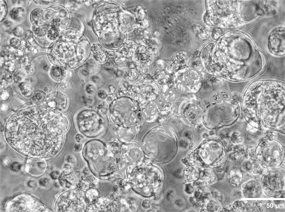

短纤维支架、自愈水凝胶制备和体内移植应用的示意图(Huan et al., 2025)

微纤维支架的仿生构建

气泡破裂法制备短纤维:利用微流控技术引入气相,使含胰岛的 Alg/HAMA 微纤维因气泡破裂断裂为短片段,长度可通过气流与预凝胶流速精准调控(流速比 1:2 时平均长度约 200 μm)。

结构仿生优势:短纤维模拟胰岛细胞外基质,提供力学支撑的同时,孔隙结构(直径 40-80 μm)促进营养交换。